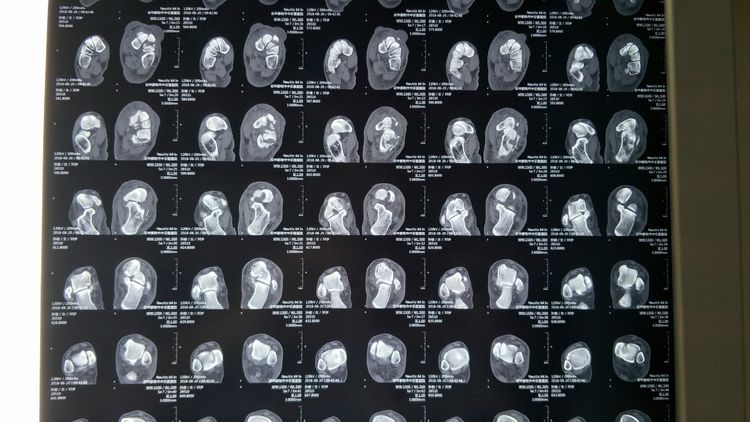

术前CT:Lisfranc关节损伤,跖跗关节脱位,内侧楔骨骨折,Chaopart(跗横关节)脱位,跟骨外侧壁骨折。